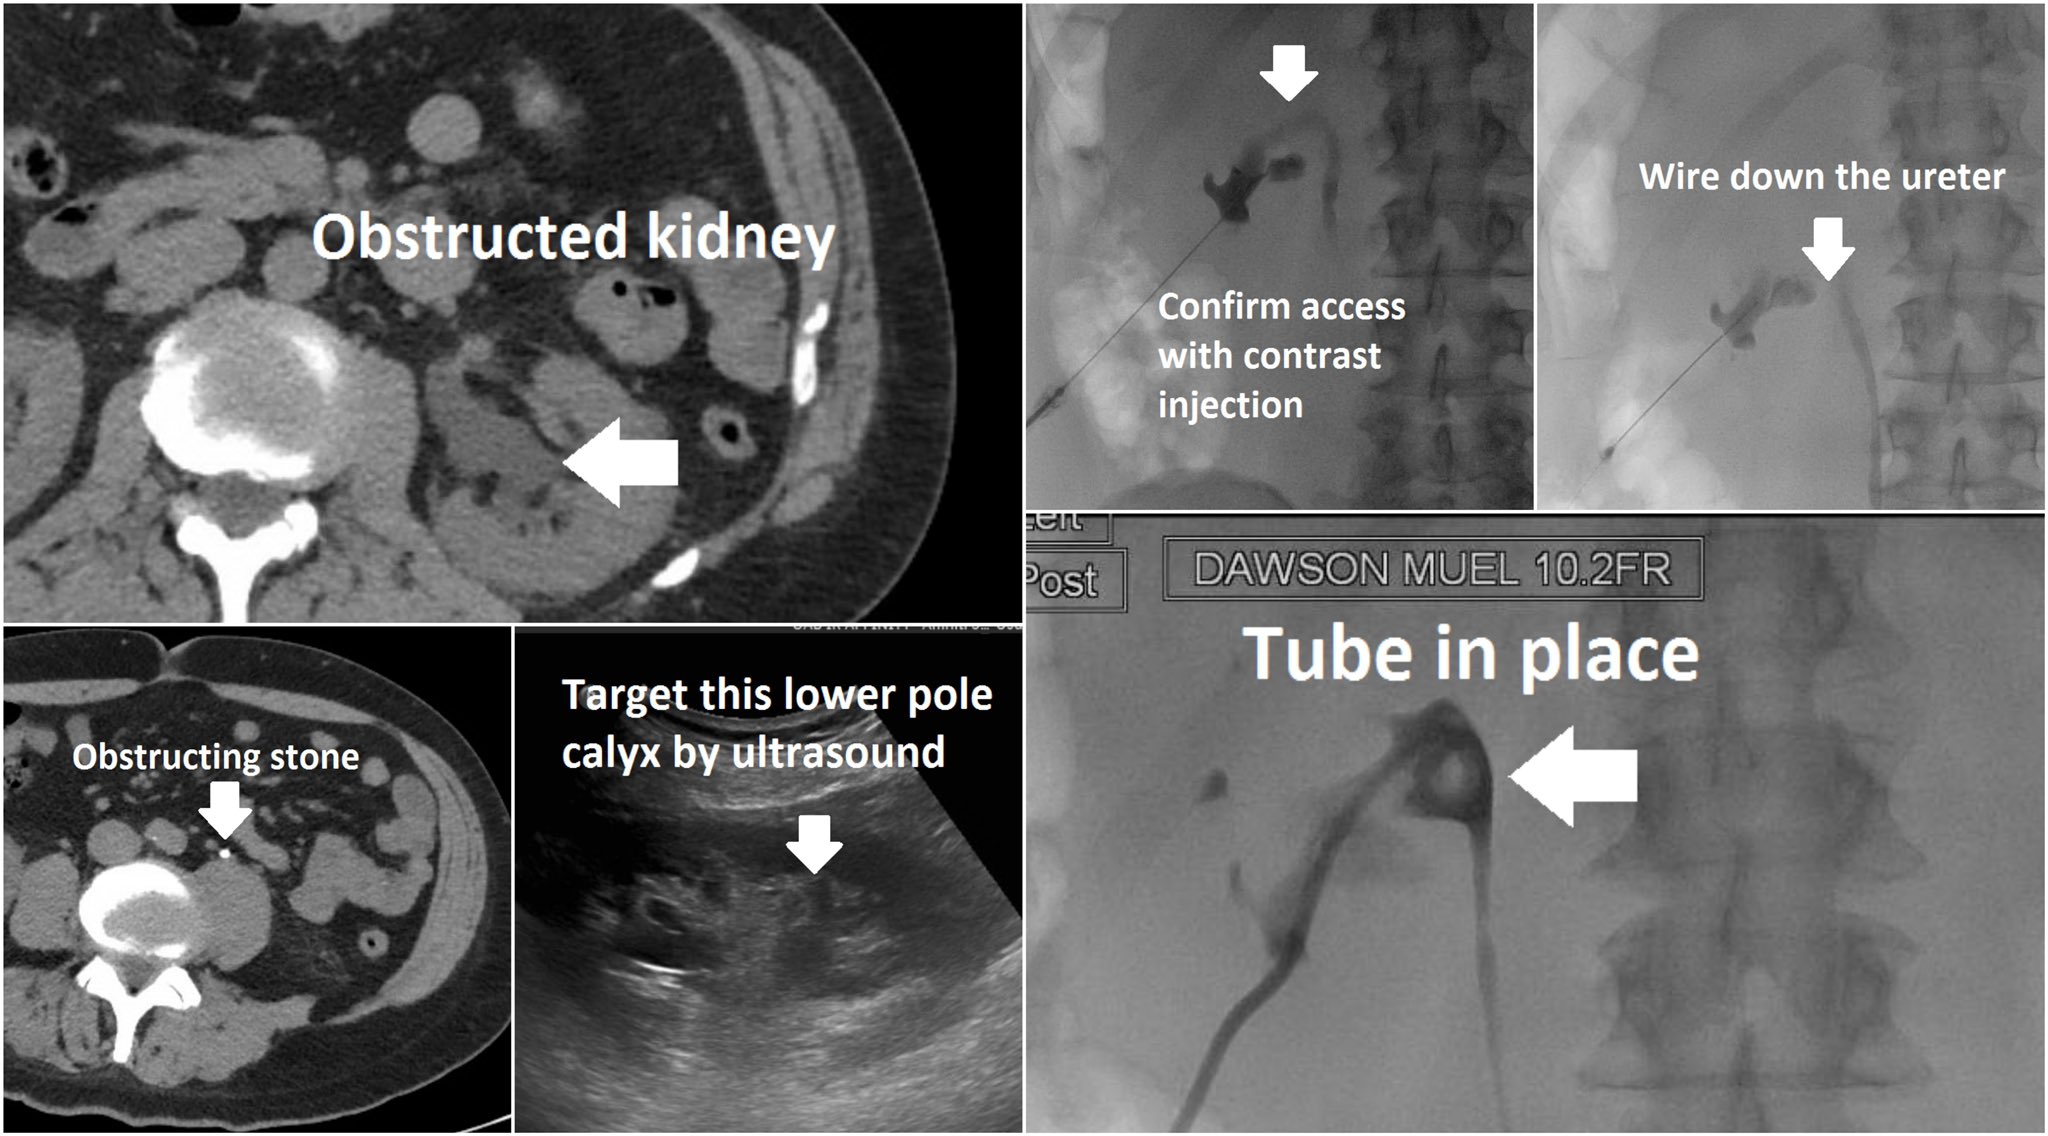

Core Videos (2019) Nephrostomy Tube Placement for Acute Upper Urinary Tract Obstruction YouTube How Do You Sleep With A Nephrostomy Tube nephrostomy tubes are usually used as a temporary solution, but this will depend on your individual situation; Our expert tips and tricks will help you. a nephrostomy tube, also known as a nephrostomy catheter or percutaneous nephrostomy, drains urine directly from. It’s a tube your healthcare provider. discover the best ways to get comfortable and sleep with. How Do You Sleep With A Nephrostomy Tube.